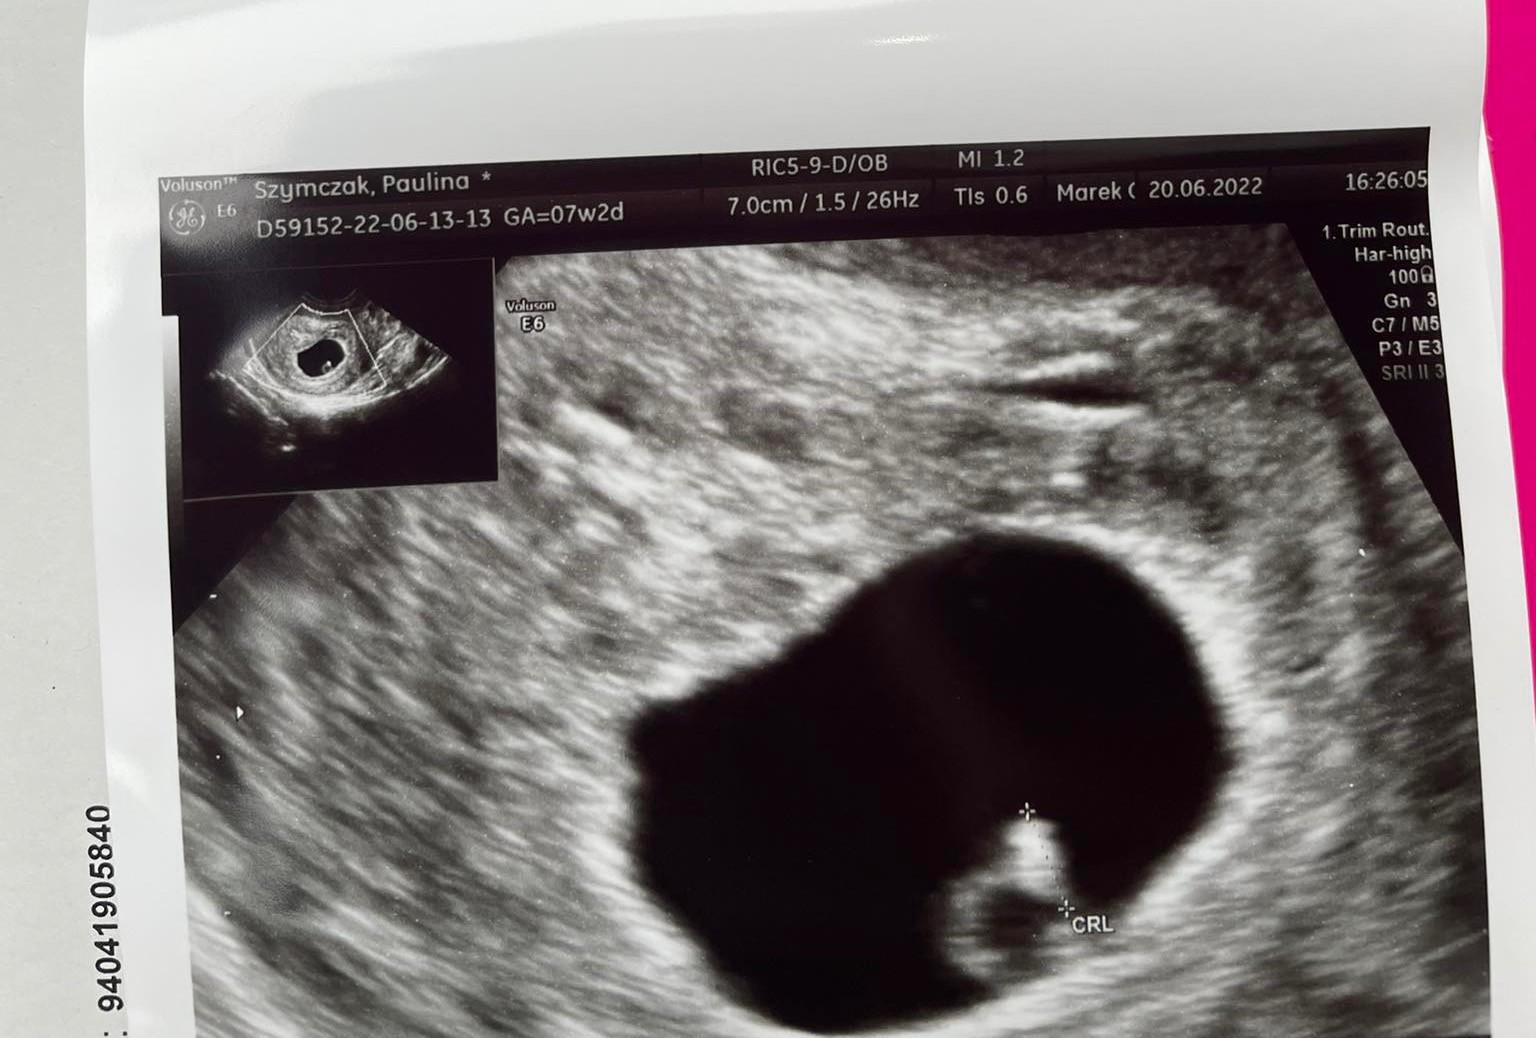

Nieregularny pęcherzyk ciazowy

Nie ukrywam ze po tym krawieniu i to jeszcze z jakims śluzem już byłam przekonana ze to po wszystkim. A lekarz na usg powiedział „ co ma wisieć nie utonie” i widzi ładną ciąże. Oczywiście mam brać dalej progesteron. Po usg miałam trochę plamienia, ale już ustało a bol pleców jest spowodowany macica w tylozgieciu. Dodatkowo suplementują się spirulina i bardzo wam to polecam, mega mi to poprawiło wyniki krwi.